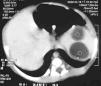

Recién nacido de sexo masculino, segundo hijo de padres jóvenes, saludables. Detectadas por ecografía fetal a las 34 semanas de gestación dos formaciones hipoecogénicas con 23 y 18 mm de diámetro en el hipocondrio izquierdo. Parto por cesárea a las 37 semanas. Test de Apgar 8/10 al primer y al quinto minutos de vida, respectivamente. Exploración física normal. Se efectuó ecografía abdominal en el cuarto día de vida, visualizándose dos formaciones quísticas en el bazo, con 24 y 19 mm de diámetro. Sin otras alteraciones intraabdominales (fig. 1). En el octavo día de vida se efectuó tomografía computarizada (TC) abdominal en la que se confirman las lesiones nodulares intraesplénicas de 23 y 27 mm (fig. 2). Período neonatal normal. Fue seguido en la consulta donde se verificó una disminución progresiva hasta su total regresión a los 5 meses de vida. Estuvo todo el tiempo asintomático y con exploración física normal.

Figura 2. TC abdominal: lesiones nodulares intraesplénicas de 23 y 27 mm.